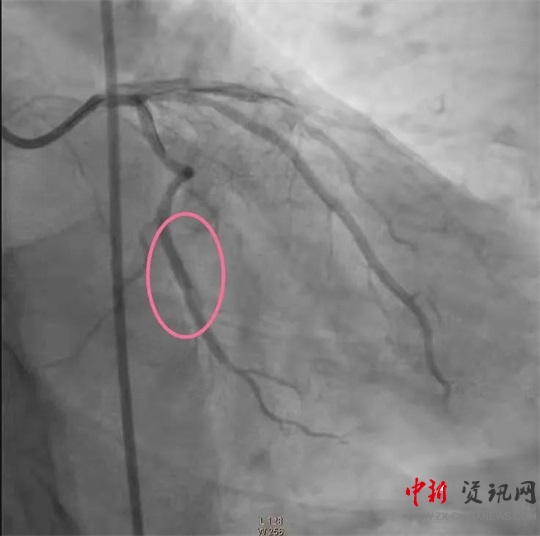

經(jīng)過一系列的術(shù)前準備并經(jīng)患者家屬同意后,立即繞行病房進入介入手術(shù)室,實施緊急手術(shù)。卒中中心團隊、胸痛中心團隊和介入團隊密切配合,為患者分別實施了腦動脈造影+主動脈弓造影+顱內(nèi)動脈瘤栓塞術(shù)+冠狀動脈造影術(shù)+經(jīng)皮冠狀動脈支架植入術(shù),成功把患者從死亡邊緣拉回。目前,患者病情穩(wěn)定,各項指標良好。

(冠脈支架植入后)